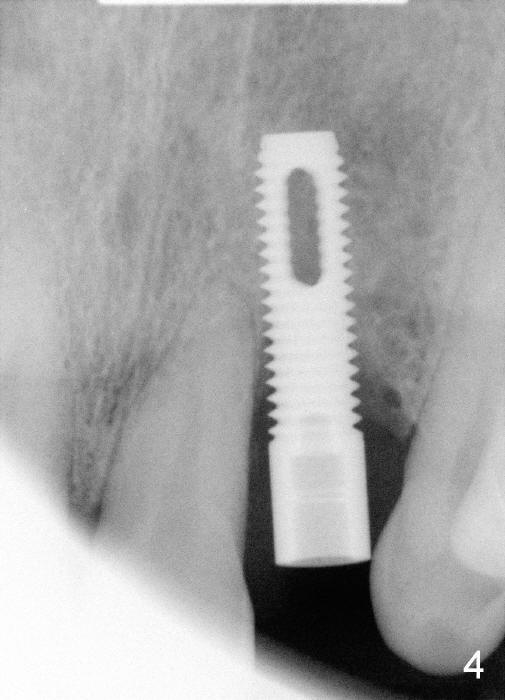

1. Place implant as lingual and apical as possible, cosmetic